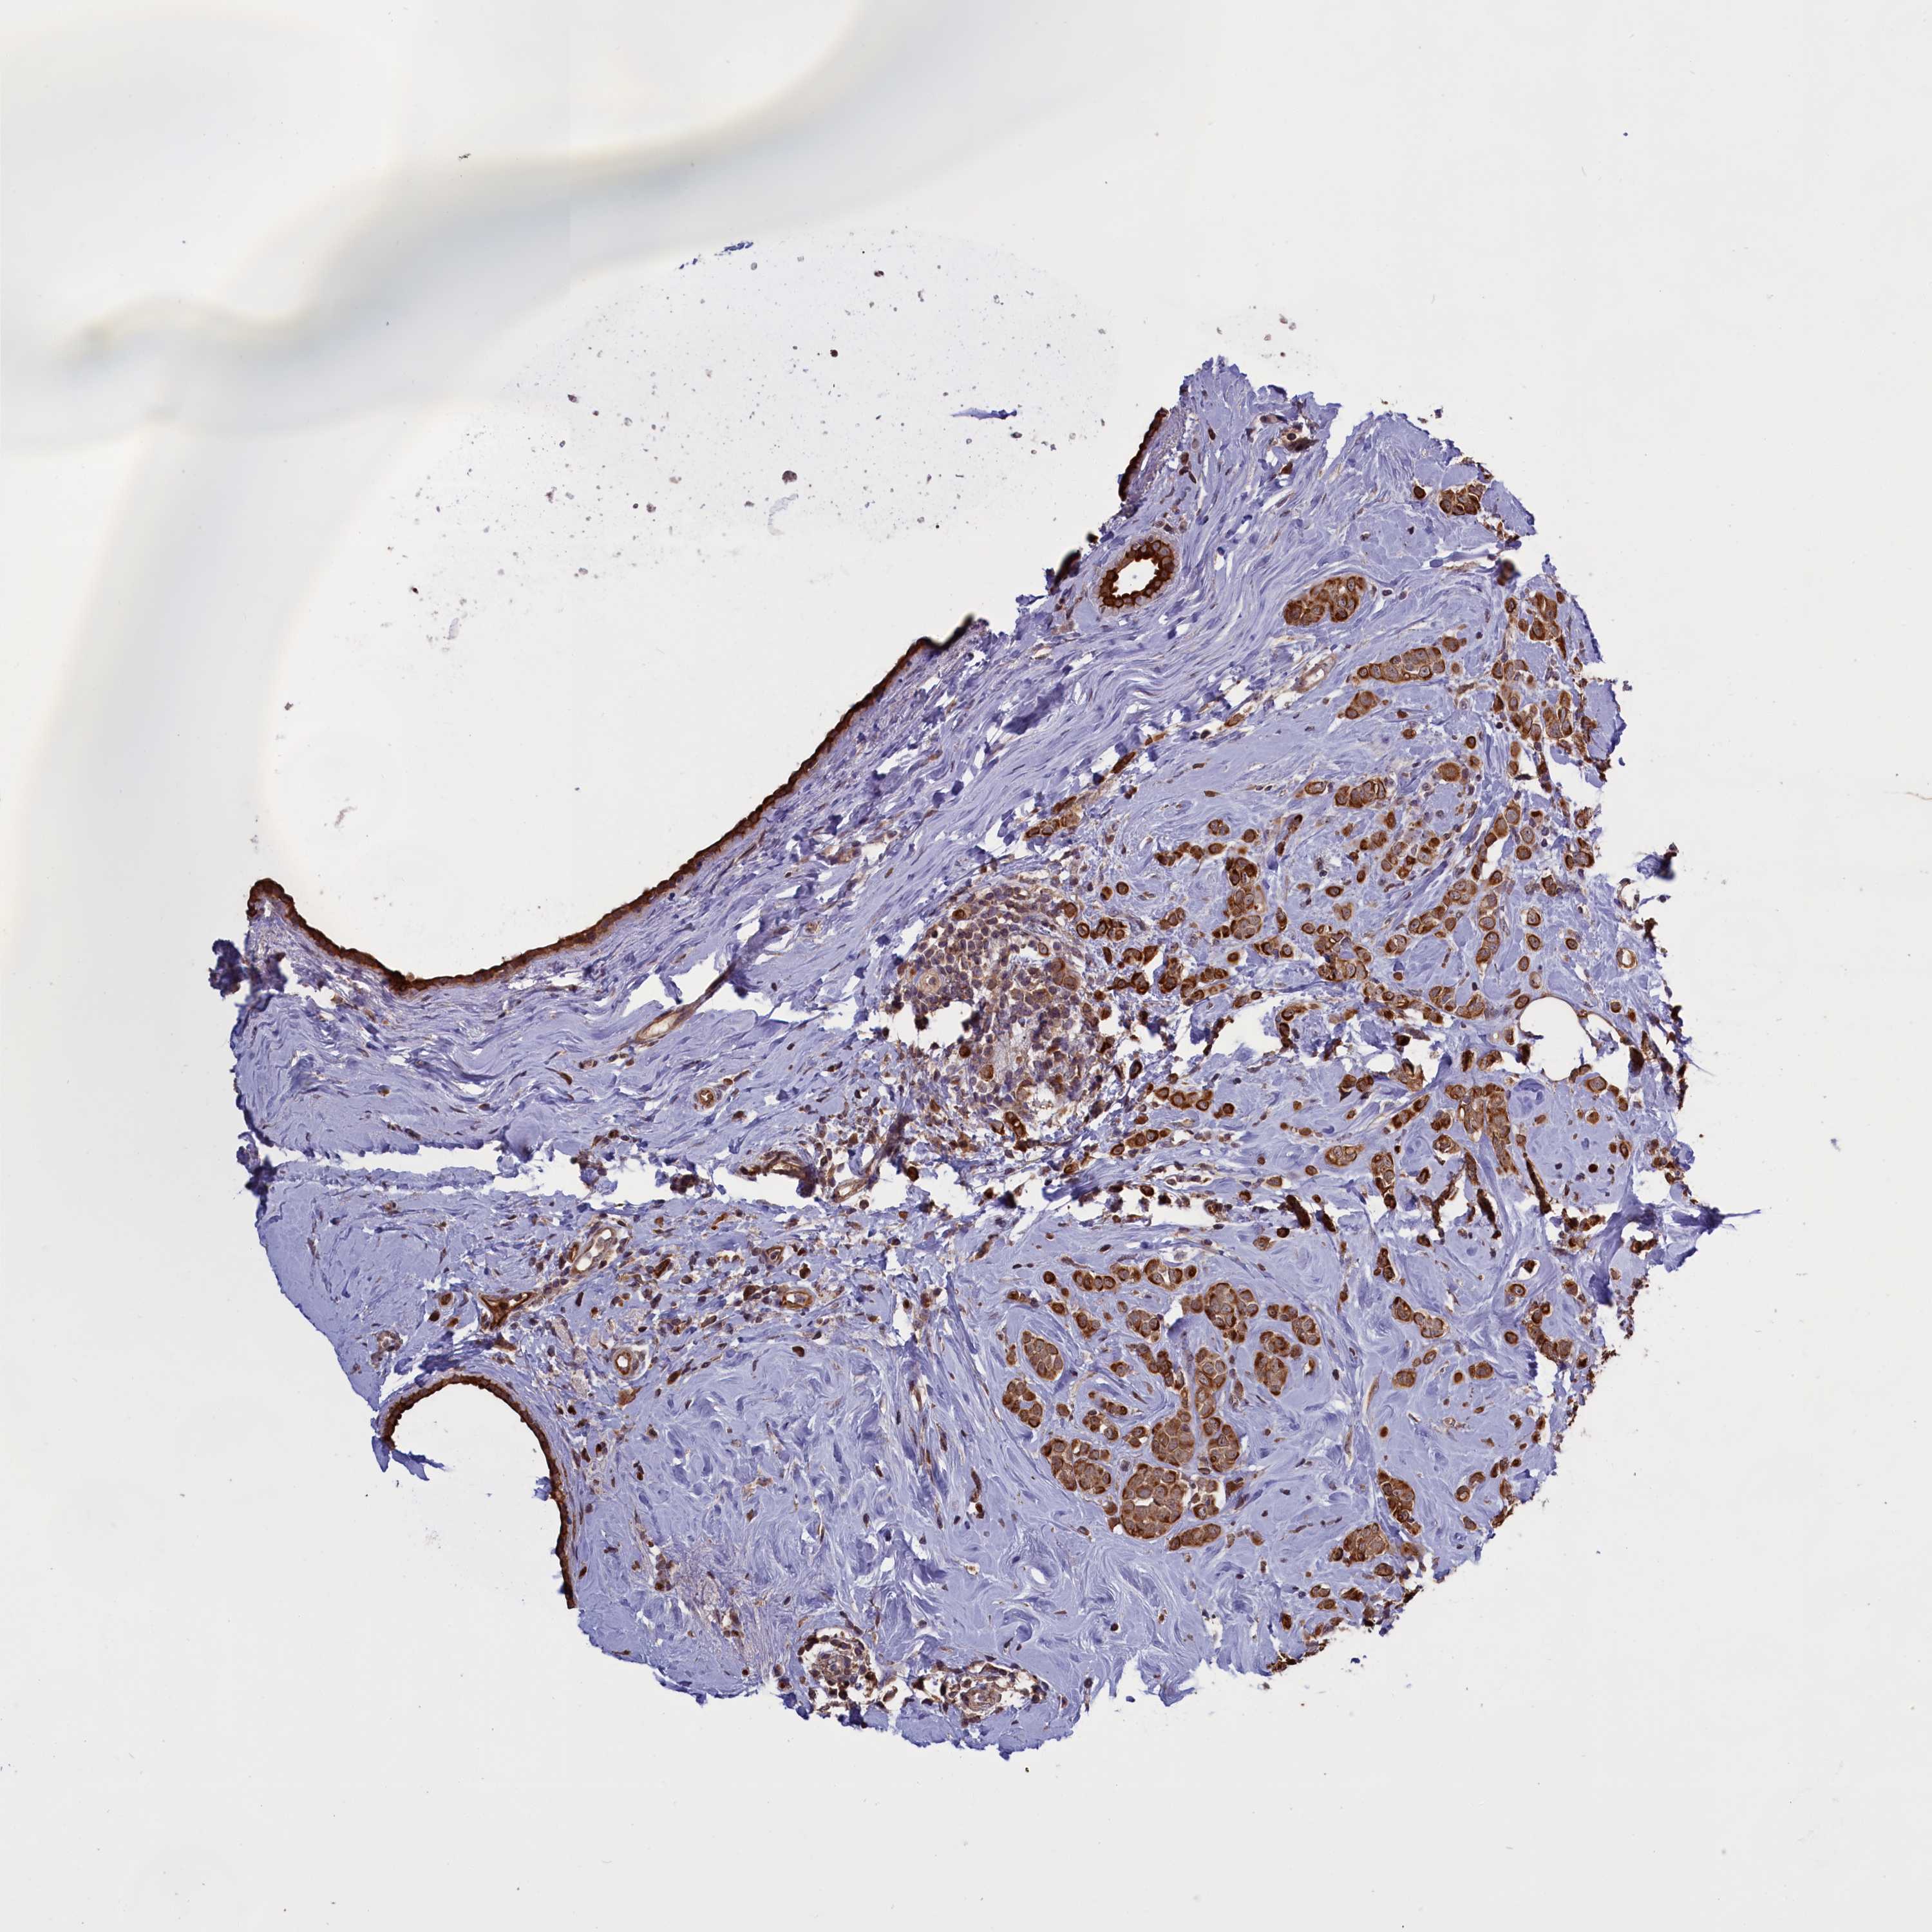

CANCER BREAST CANCER Show tissue menu

BRCA TCGA BRCA VALIDATION PROTEIN EXPRESSION